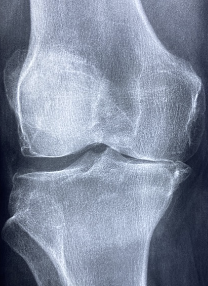

무릎은 하반신과 상반신을 연결하는 관절로서, 대퇴골, 종아리뼈, 장골로 이루어져 있습니다. 몸의 무게 중심을 지탱하고, 다양한 움직임을 수행하는 중요한 관절 중 하나입니다. 하지만, 무릎은 무거운 무게를 지탱하며 일상생활에서 노출되는 부위이기 때문에 다양한 질환과 부상의 위험이 있습니다. 적극적인 관리와 근력 강화를 통해 무릎 건강을 유지하는 것이 중요합니다.

무릎 연골 정보

무릎 연골 손상 증상

무릎 연골은 외상이나 퇴행성 변화에 의해 손상될 수 있으며, 이 경우 다음과 같은 증상이 나타날 수 있습니다.

- 무릎에 통증이 있으며, 특히 무릎을 구부리거나 쪼그리는 동작에서 심해집니다.

- 무릎에 부기가 생기고, 때로는 관절액이 축적되어 물이 차는 느낌이 들 수 있습니다.

- 무릎을 움직일 때 삐걱거리는 소리가 나거나 이물감이 느껴질 수 있습니다.

- 무릎이 잠기거나 불안정하게 느껴지며, 운동 제한이 생길 수 있습니다.